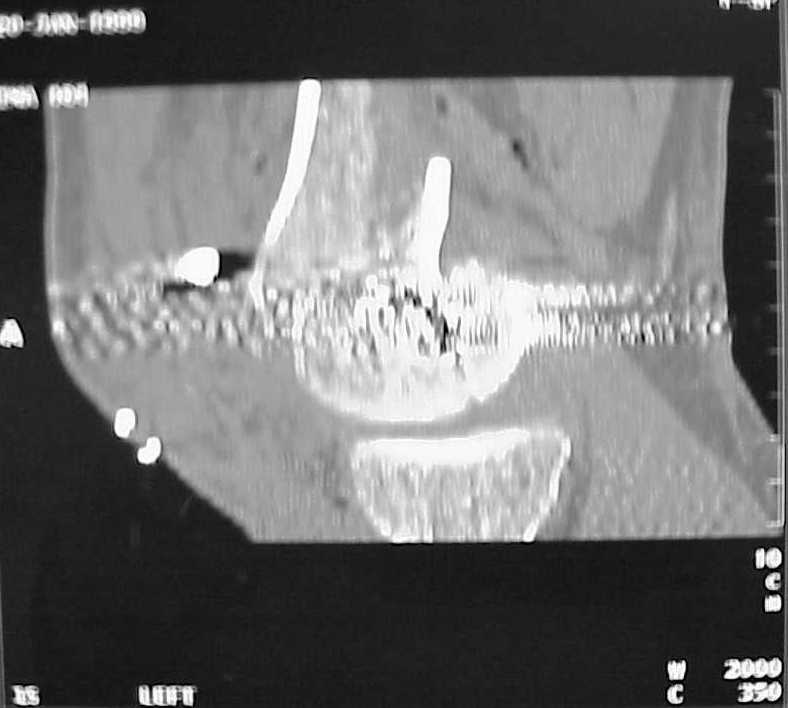

So I think a TAC of the knee could be useful.

A CT and knee xrays would help identify lateral condyle comminution and/or a "hoffa fragment" of the posterior condyle. I am concerned that the lateral cortex is not sufficient to give purchase for a retrograde IMN. blocking screws could improve this as a possibility. A long blade or LISS if avaible would be my secondary choices. Good luck. Any chance you can get these cases transferred earlier when it

Мы пошли на операцию с планом попытаться сделать закрытый интрамедулярный, а не получится - сделать аппаратом. Посчитали, что получилось, хотя на еженедельной конференции ожидаются некоторые проблемы с объяснениями ;-)

Насчет стабильности для ранней нагрузки, конечно, сомнительно, но при таком повреждении ранняя нагрузка противопоказана в любом случае. Для ранних движений Должно хватить. Снимки в следующем сообщении.

воспользовались для репозиции, см. приложение.